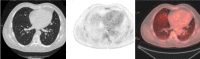

Current widespread use of cross-sectional imaging has led to exponential rise in detection of solitary pulmonary nodules (SPNs). Whilst large numbers of these are benign 'incidentalomas', lung cancers presenting as SPNs are often early disease, which have good prognosis. Therefore, there is rising demand and expectation for more accurate, non-invasive, diagnostic tests to characterize SPNs, aiming to avoid missed or delayed diagnosis of lung cancer. There are wide differential diagnoses of benign and malignant lesions that manifest as SPNs. On conventional imaging, the morphological features supporting benignity include stable small nodule size, smooth demarcated margins, and calcifications. Lack of significant contrast enhancement is also more suggestive of benign nodules. With improved understanding of tumor biology, for instance neo-vascularization and increased vascular permeability, imaging techniques such as dynamic contrast-enhanced computed tomography (CT) provide details on contrast uptake and wash-out kinetics, which is more closely reflecting the physiological and pathological phenomena. Positron emission tomography (PET) using 18fluorine-fluoro-deoxyglucose ((18)F-FDG) is a well-established functional imaging technique, for which one of the most common indications is differentiating between benign and malignant SPNs. Combined PET-CT integrates the anatomical, morphological and metabolic aspects in a single examination, improving overall diagnostic accuracy. Semi-quantitative analysis in FDG-PET imaging is based on measurement of maximum standardized uptake values (SUVmax). SUVmax analysis may become more useful as an assessment of tumor biology in future risk stratification models for cancers. Dual-time point FDG-PET imaging, dual-energy CT, perfusion CT, magnetic resonance (MR) imaging using dynamic contrast enhancement or diffusion-weighted imaging (DWI) techniques, are among the growing armamentarium for diagnostic imaging of SPNs. Provided there is no unacceptably high procedural or operative risk, tissue diagnosis by resection or percutaneous biopsy of SPN should be advocated in those patients identified as at moderate or high risk of malignancy, based on clinical stratification.